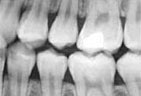

Digital X-rays

We use state of the art digital X-rays and digital cameras to help with an accurate diagnosis of any concerns. Digital X-rays use less radiation to get a diagnostic picture of your teeth and they help the environment by eliminating the use of chemicals to process the film.

Digital x-ray image